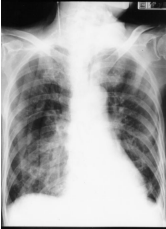

15. 一 70 歲男性,過去有抽菸病史 30 年 (1 pack/d) 咳嗽有痰且呼吸困難 3 天,理學檢查發現肺 - 肝界線 (lung-liver border) 在第 6 肋間,兩側肺野呼吸音對稱且有喘鳴,病人胸部 X 光如附圖二 示,病人可能發生: (A) 右側氣胸 (B) COPD 急性發作 (C) 肺血管栓塞 (D) 肺纖維化症 (E) 異物吸入症候群